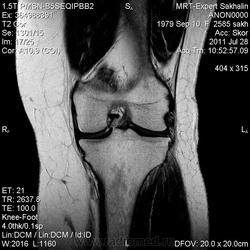

Коленный сустав

Подглядела случай у коллеги.

Что это может быть?

Не вижу криминала. А на что жалуется девушка?

P.S. В костях - это, скорее всего, резидуальный красный костный мозг.